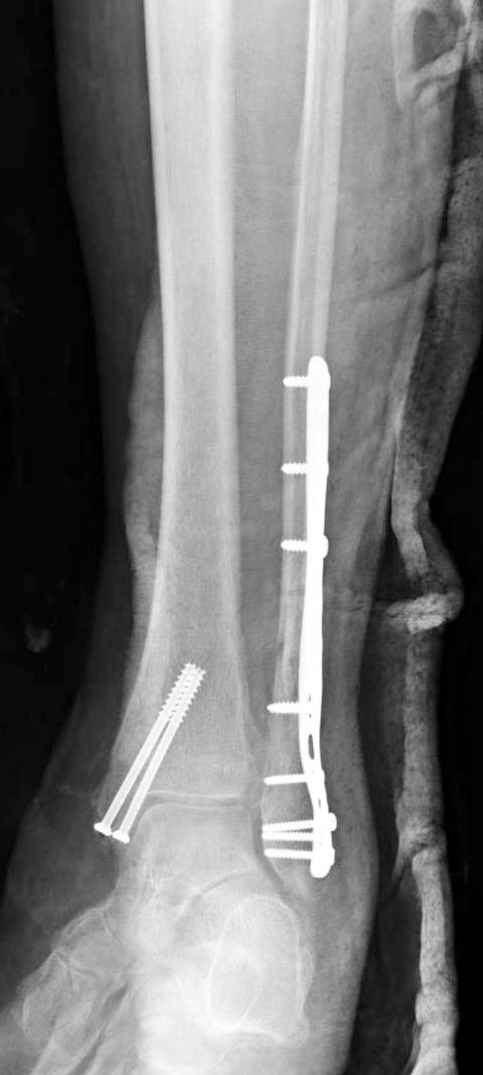

Здесь финальный снимок 73 летней с

сопутствующей шизофренией, латерально бридж

пластину (соединили дистальный конец с диафизом не трогая место перелома) и медиально перкутанно

двумя шурупами. В этам случае без гипса не

обойтись.